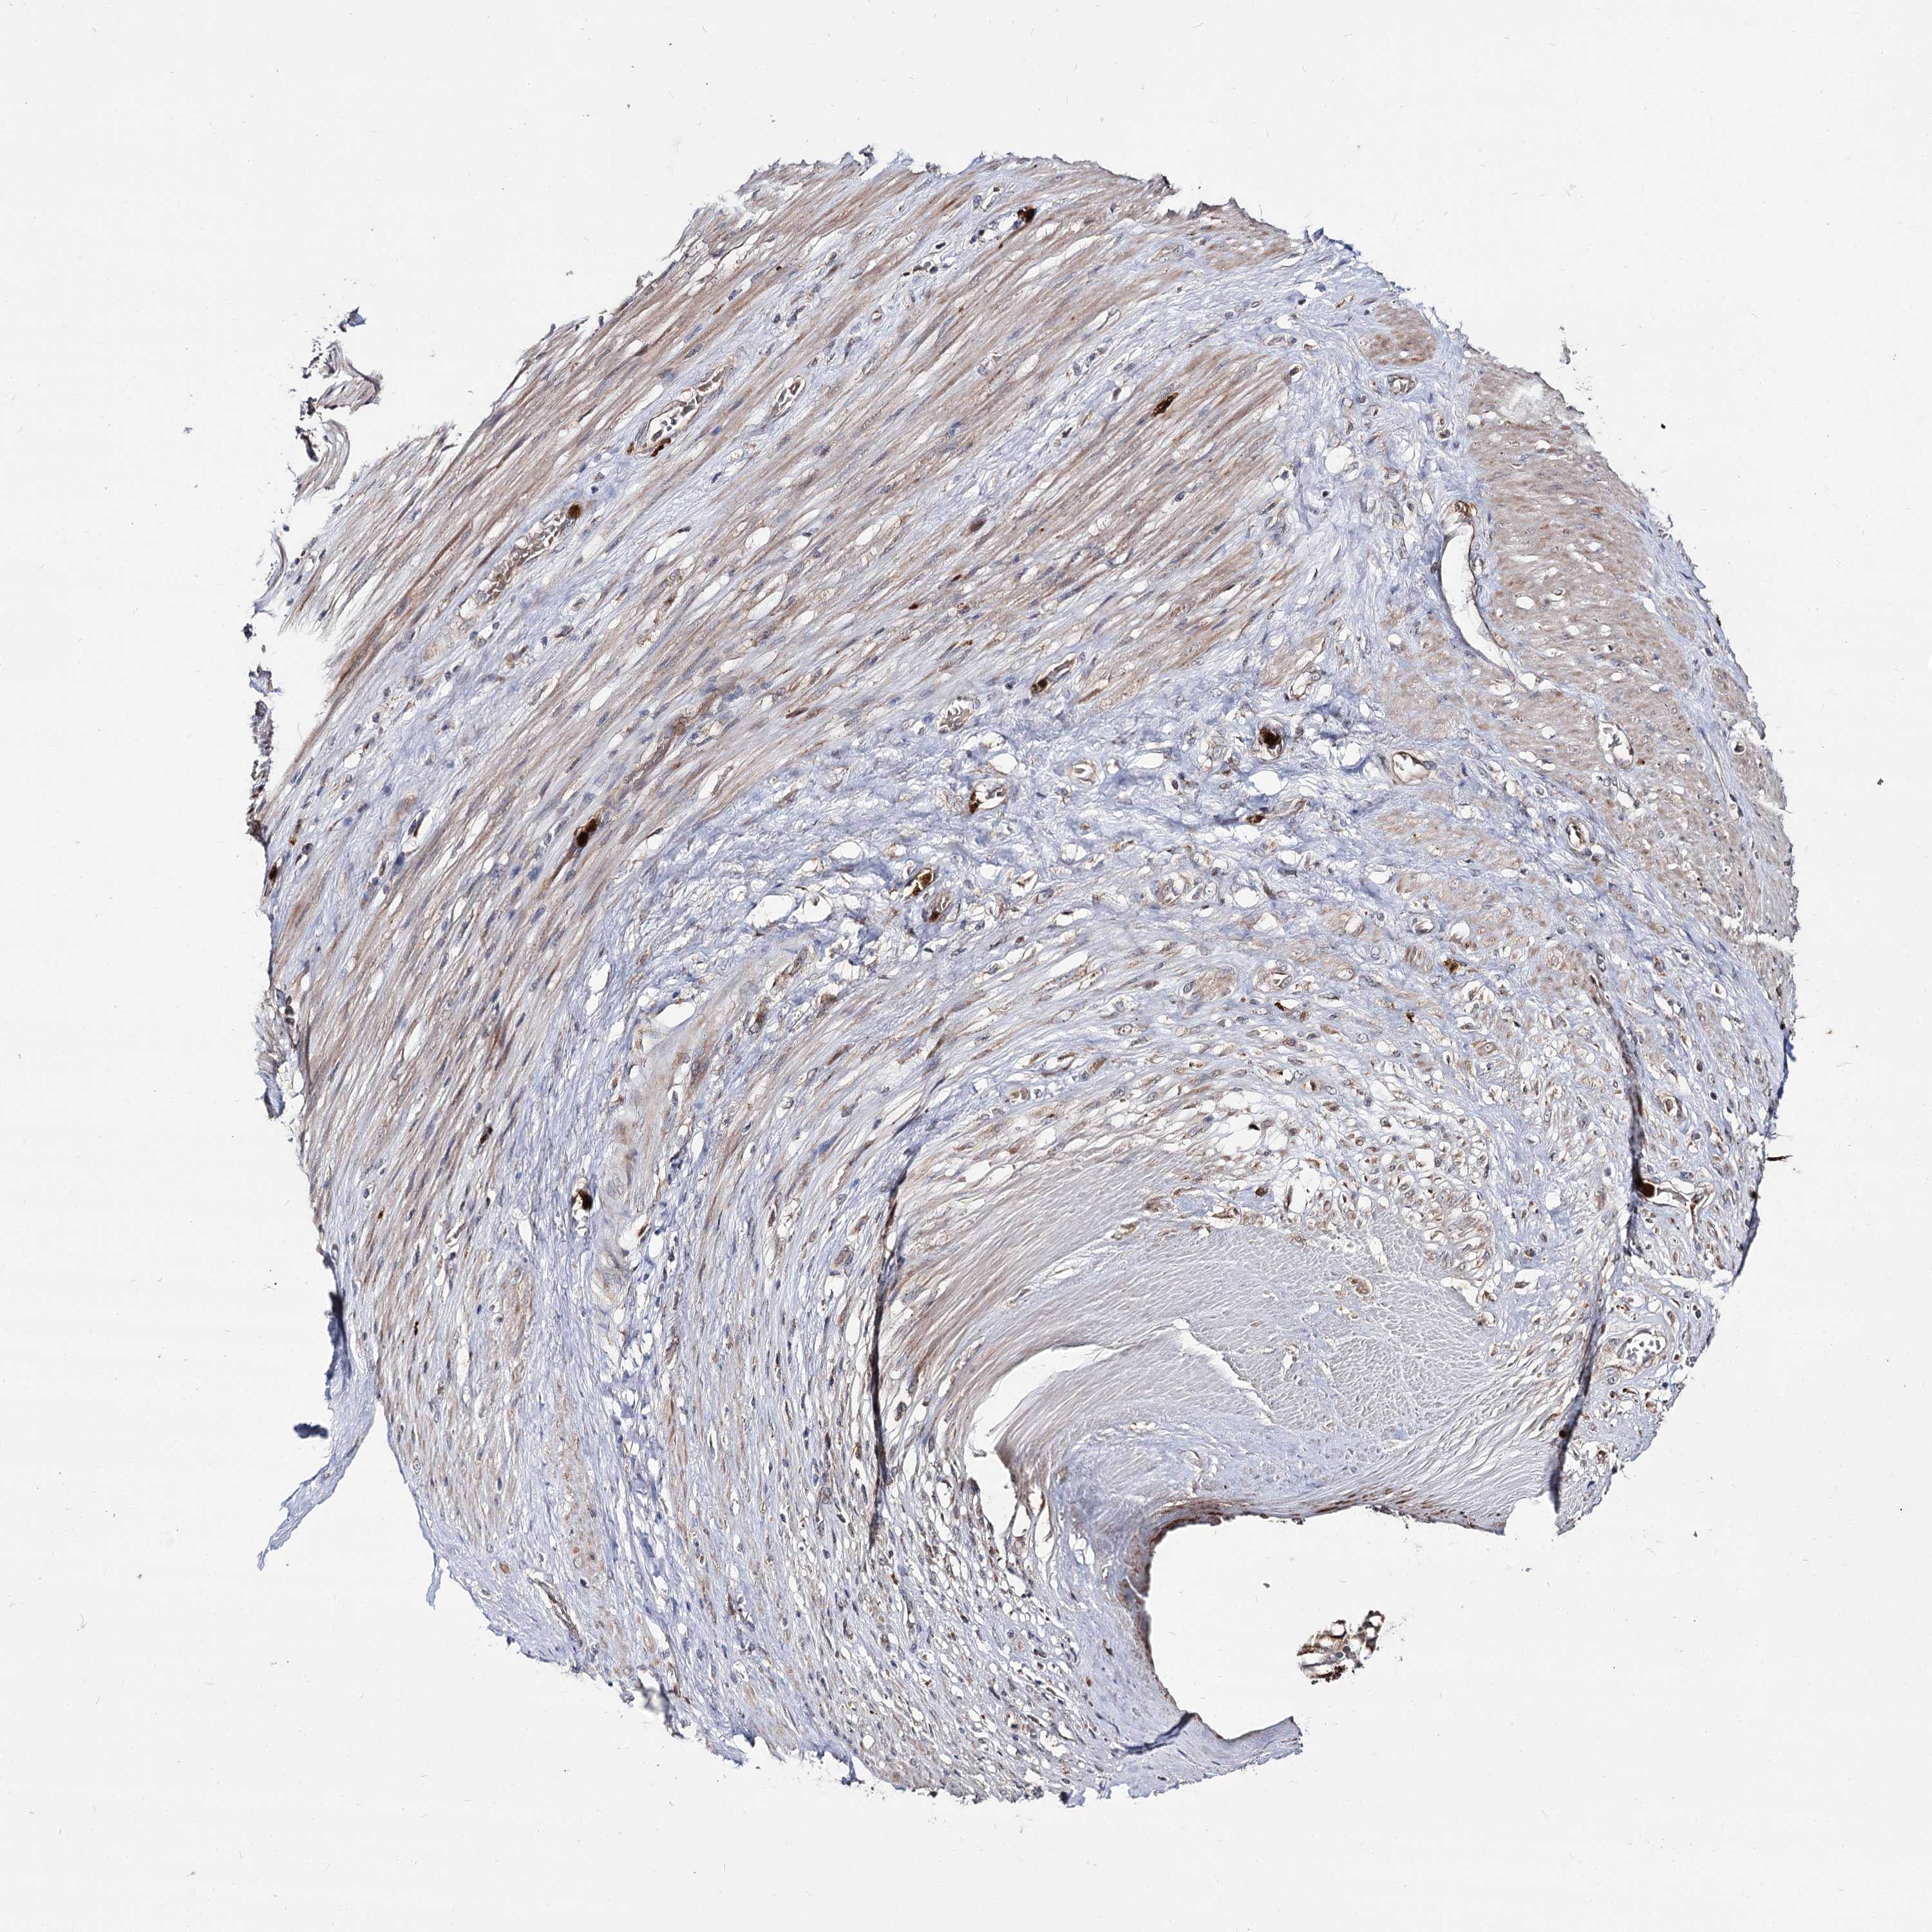

STOMACH CANCER - Protein expressioni

A mouse-over function shows sample information and annotation data. Click on an image to view it in a full screen mode. Samples can be filtered based on level of antibody staining by selecting one or several of the following categories: high, medium, low and not detected. The assay and annotation is described here.

Note that samples used for immunohistochemistry by the Human Protein Atlas do not correspond to samples in the TCGA dataset.

Antibody stainingi

Antibody staining in the annotated cell types in the current human tissue is reported as not detected, low, medium, or high, based on conventional immunohistochemistry profiling in selected tissues. This score is based on the combination of the staining intensity and fraction of stained cells.

Each image is clickable and will lead to virtual microscopy that enables deeper exploration of all samples and also displays staining intensity scores, fraction scores and subcellular localization as well as patient and tissue information for each sample.

Antibody HPA038040

Staining

High

Medium

Low

Not detected

Intensity

Strong

Moderate

Weak

Negative

Quantity

>75%

75%-25%

<25%

None

Location

Nuclear

Cytoplasmic/membranous

Cytoplasmic/membranous,nuclear

Adenocarcinoma, NOS

Adenocarcinoma, High grade